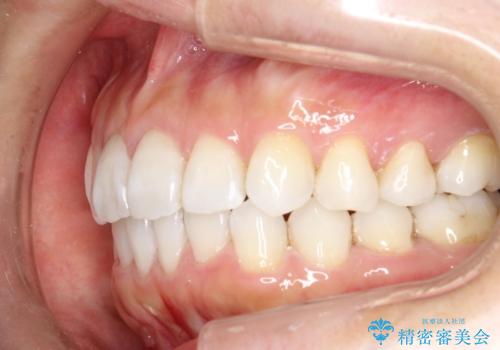

抜歯せずに八重歯のマウスピース矯正

八重歯がシビアな場合、抜歯をしないと治せないケースもありますが、奥歯の位置関係を修正したり、歯のサイズダウンを行うことで、抜歯をせずに改善できる場合もたくさんあります。